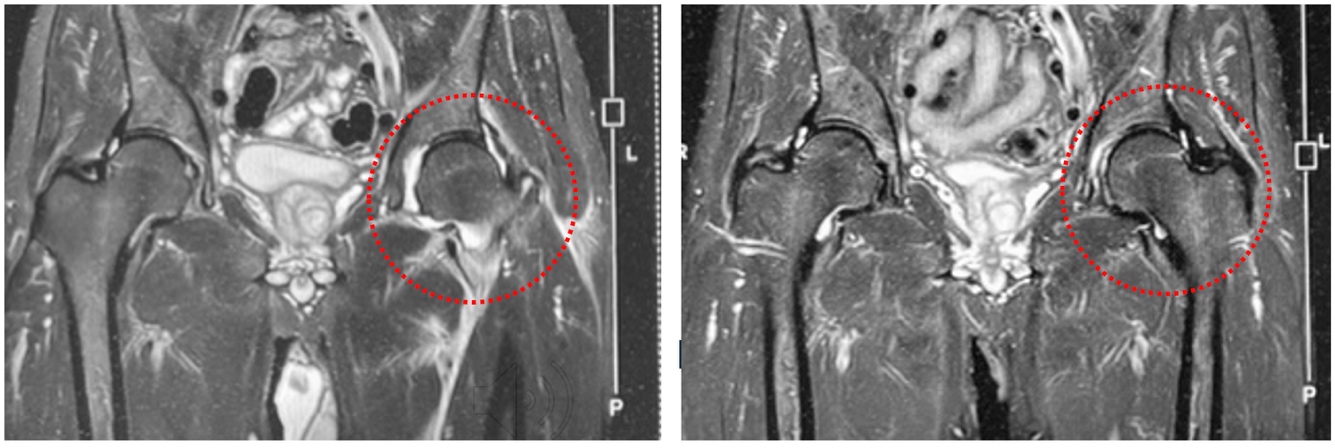

左図:股関節内水腫 → 右図:股関節内水腫が3ヶ月後に消失

左図:股関節周辺筋群炎症波及 → 右図:周囲筋群への炎症が消失

乳歯髄幹細胞培養上清液には、体の回復を助ける成分が多く含まれており、炎症をしずめる働きがあります。そのため、関節にたまった水(関節内水腫)や、周囲の筋肉に広がった炎症をやわらげ、回復を促します。この方は強い痛みのため歩くことが困難でしたが、培養上清液の注射を5回行った結果、MRI画像と症状の両方が改善し、日常生活を問題なく送れるようになりました。